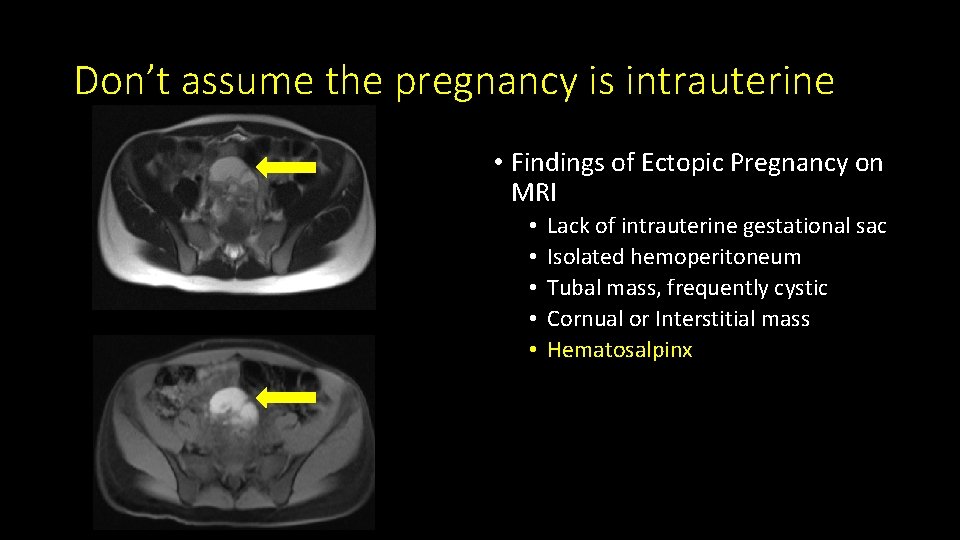

Don’t assume the pregnancy is intrauterine • Findings of Ectopic Pregnancy on MRI • • • Lack of intrauterine gestational sac Isolated hemoperitoneum Tubal mass, frequently cystic Cornual or Interstitial mass Hematosalpinx

Don’t assume the pregnancy is intrauterine • Findings of Ectopic Pregnancy on MRI • • • Lack of intrauterine gestational sac Isolated hemoperitoneum Tubal mass, frequently cystic Cornual or Interstitial mass Hematosalpinx

Don’t assume the pregnancy is intrauterine • Findings of Ectopic Pregnancy on MRI • • • Lack of intrauterine gestational sac Isolated hemoperitoneum Tubal mass, frequently cystic Cornual or Interstitial mass Hematosalpinx

Don’t assume the pregnancy is intrauterine • Findings of Ectopic Pregnancy on MRI • • • Lack of intrauterine gestational sac Isolated hemoperitoneum Tubal mass, frequently cystic Cornual or Interstitial mass Hematosalpinx